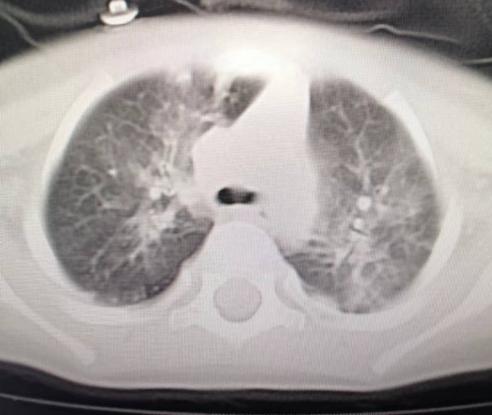

近日儿三科收住了一位“咳嗽20余天,间断发热半月”严重呼吸道感染的1岁小宝宝,结合宝宝入院时精神欠佳及肺部CT考虑重症肺炎。

肺部CT双肺多发感染并实变

啥病原体这么厉害?医生入院后予吸氧等对症治疗并完善了纤维支气管镜肺泡灌洗,灌洗液病原体宏基因显示腺病毒感染合并烟曲霉、微小根毛霉真菌感染,病情严重,转至儿童监护室,根据病原体结果继续免疫球蛋白、抗真菌、短疗程激素等治疗后病情好转。答案揭晓,原来是腺病毒感染,后期合并了真菌感染。